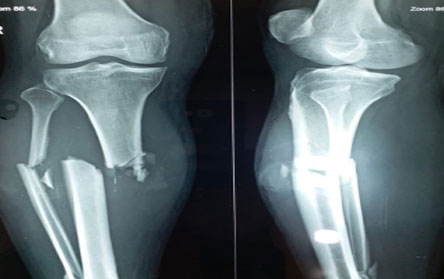

Trauma surgery:

Trauma surgery is a surgical specialty that utilizes both operative and non-operative management to treat traumatic injuries.

The Center of Orthopedics KUMAR ORTHO HOSPITAL ,Patna, offers the entire spectrum of modern orthopedic management, which is effective, patient - friendly & result oriented. In a nutshell, it is one stop treatment for all orthopedic ailments and fractures with emphasis on avoidance of complications, rapid mobilization, decreased period of confinement and an early return to normalcy.